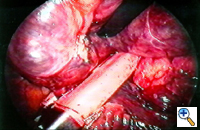

Group III: multiple bullae with underlying lung diffusely emphysematous (Figure 2)

| Figure 1: Operative view at thoracotomy of a single bulla with normal underlying lung. | Figure 2: Operative view at thoracotomy of multiple bullae with underlying lung with diffuse emphysema. |